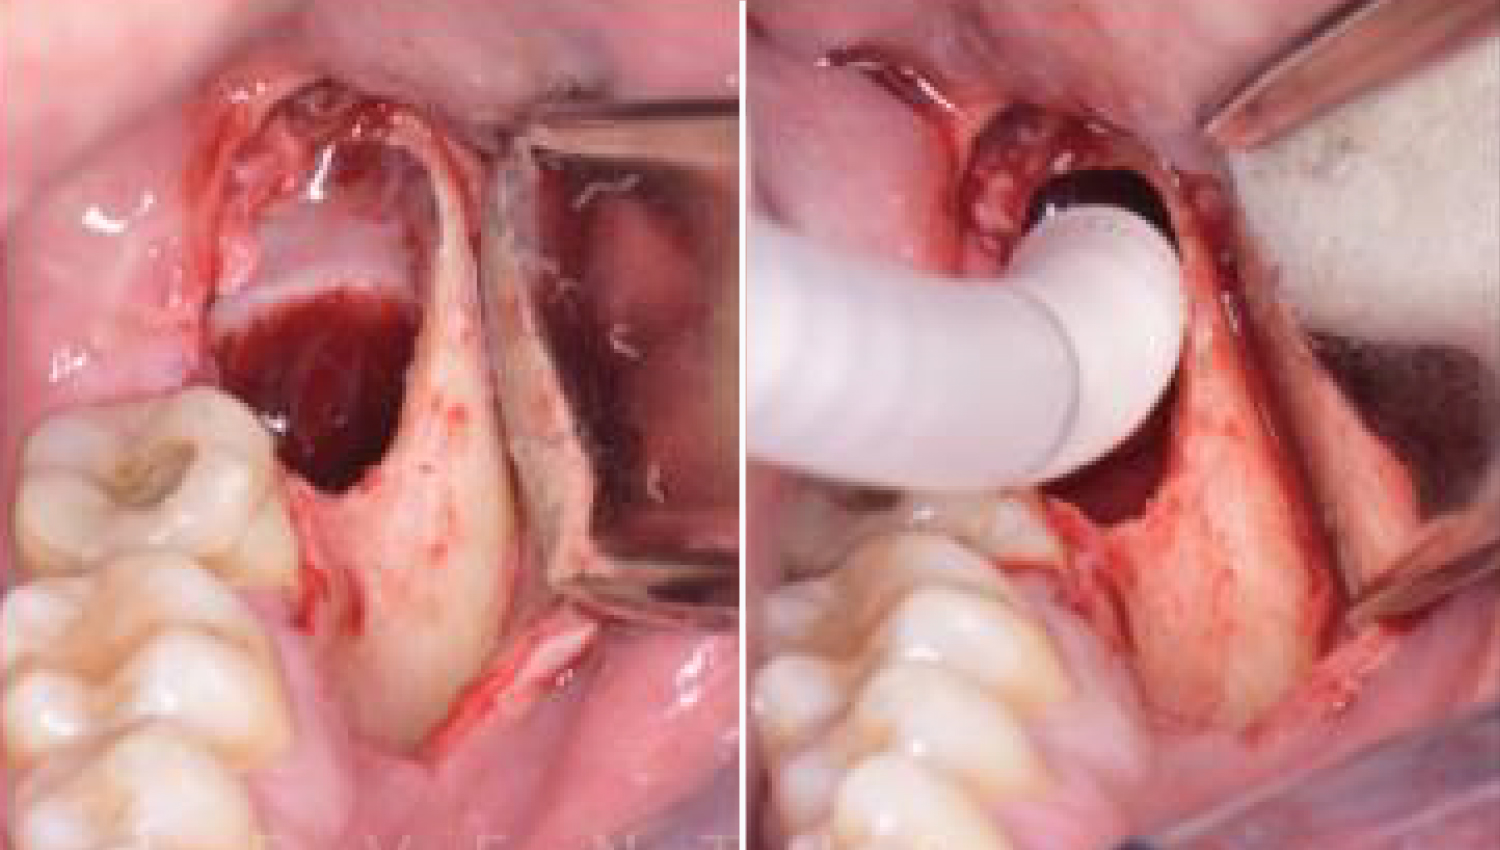

4. Reconstruction of the bone defectusing Powerbone Putty and Crunch.

5.Grafted with Powerbone Dental Putty and PowerBone granules.